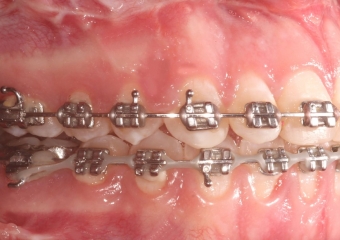

Mordida após a cirurgia - Clínica Cliniface

Mordida após a cirurgia